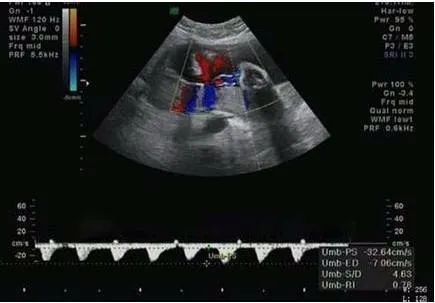

妊娠期为了保证母胎健康和宝宝正常的发育,所需要做的检查是很多的,一般当怀孕20周以后就可以做脐血流的检查,这也是检查项目之一。脐血流是指脐带中血液流动的情况,脐带中一般包括三条血管,其中两条是动脉,一条是静脉。脐血流是反映了这三条血管的情况,血流一般通过S/D来进行表达,S一般是指收缩期血流速度,D一般是指舒张期的血流速度。这个数值反映了脐带血流的阻力。数值越高反应血流阻力越大速度越慢。

S/D正常情况下和孕周相关,不能大于相应孕周的参考范围的最大值,如果大于相应孕周参考范围最大值,往往提示血流慢了胎儿可能存在缺氧或者血液供应不足的情况,这种情况有可能引起胎儿生长发育不全。因此在孕期做b超的时候一定要注意脐血流是不是正常,如果异常,应及时检查原因。

一般在20周以前检测脐血流意义不大,随着孕周的增加,脐血流呈下降趋势,脐血流正常值在24周时其平均值为3.5,上限为4.25,超过上限为异常。孕28周后S/D应小于3,从孕25周到41周,大多数 孕妈 的S/D比值几乎呈直线从2.8降至2.2左右。一般妊娠晚期S/D值小于或等于3.0...为正常。

脐血流检查只是看胎儿发育情况的一个方面,很多时候需要根据各种情况来综合评估判断,不是绝对的仅凭这一项就能判断胎儿宫内缺氧的,因为脐血流的检测值及其准确性也要受很多因素的影响,如胎儿的体重,胎盘的情况,测量的部位等等,如果孕晚期随着孕周的增加,S/D比值并没有规律的下降,反而出现了升高的现象。这就说明可能有胎儿发育不良、宫内缺氧、脐带绕颈等情况,如果只是高出一点点其实也可以不用治疗,只要观察就可以了,最重要的就是要听取医生的建议。